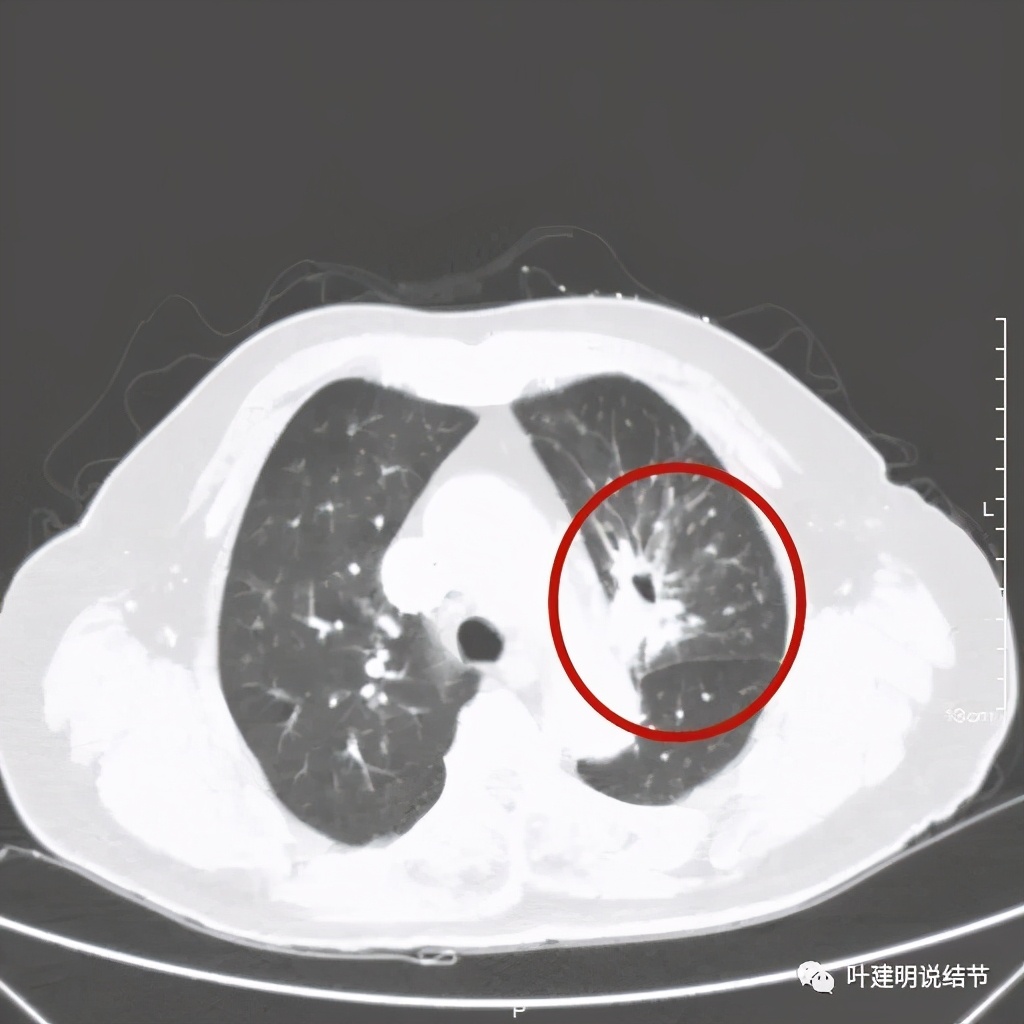

肺窗见原左上叶巨大占位已经明显缩小,甚至几乎不见了!而且上图示左上叶支气管清晰可见,内壁变光滑。纵隔窗增强又是如何的呢?